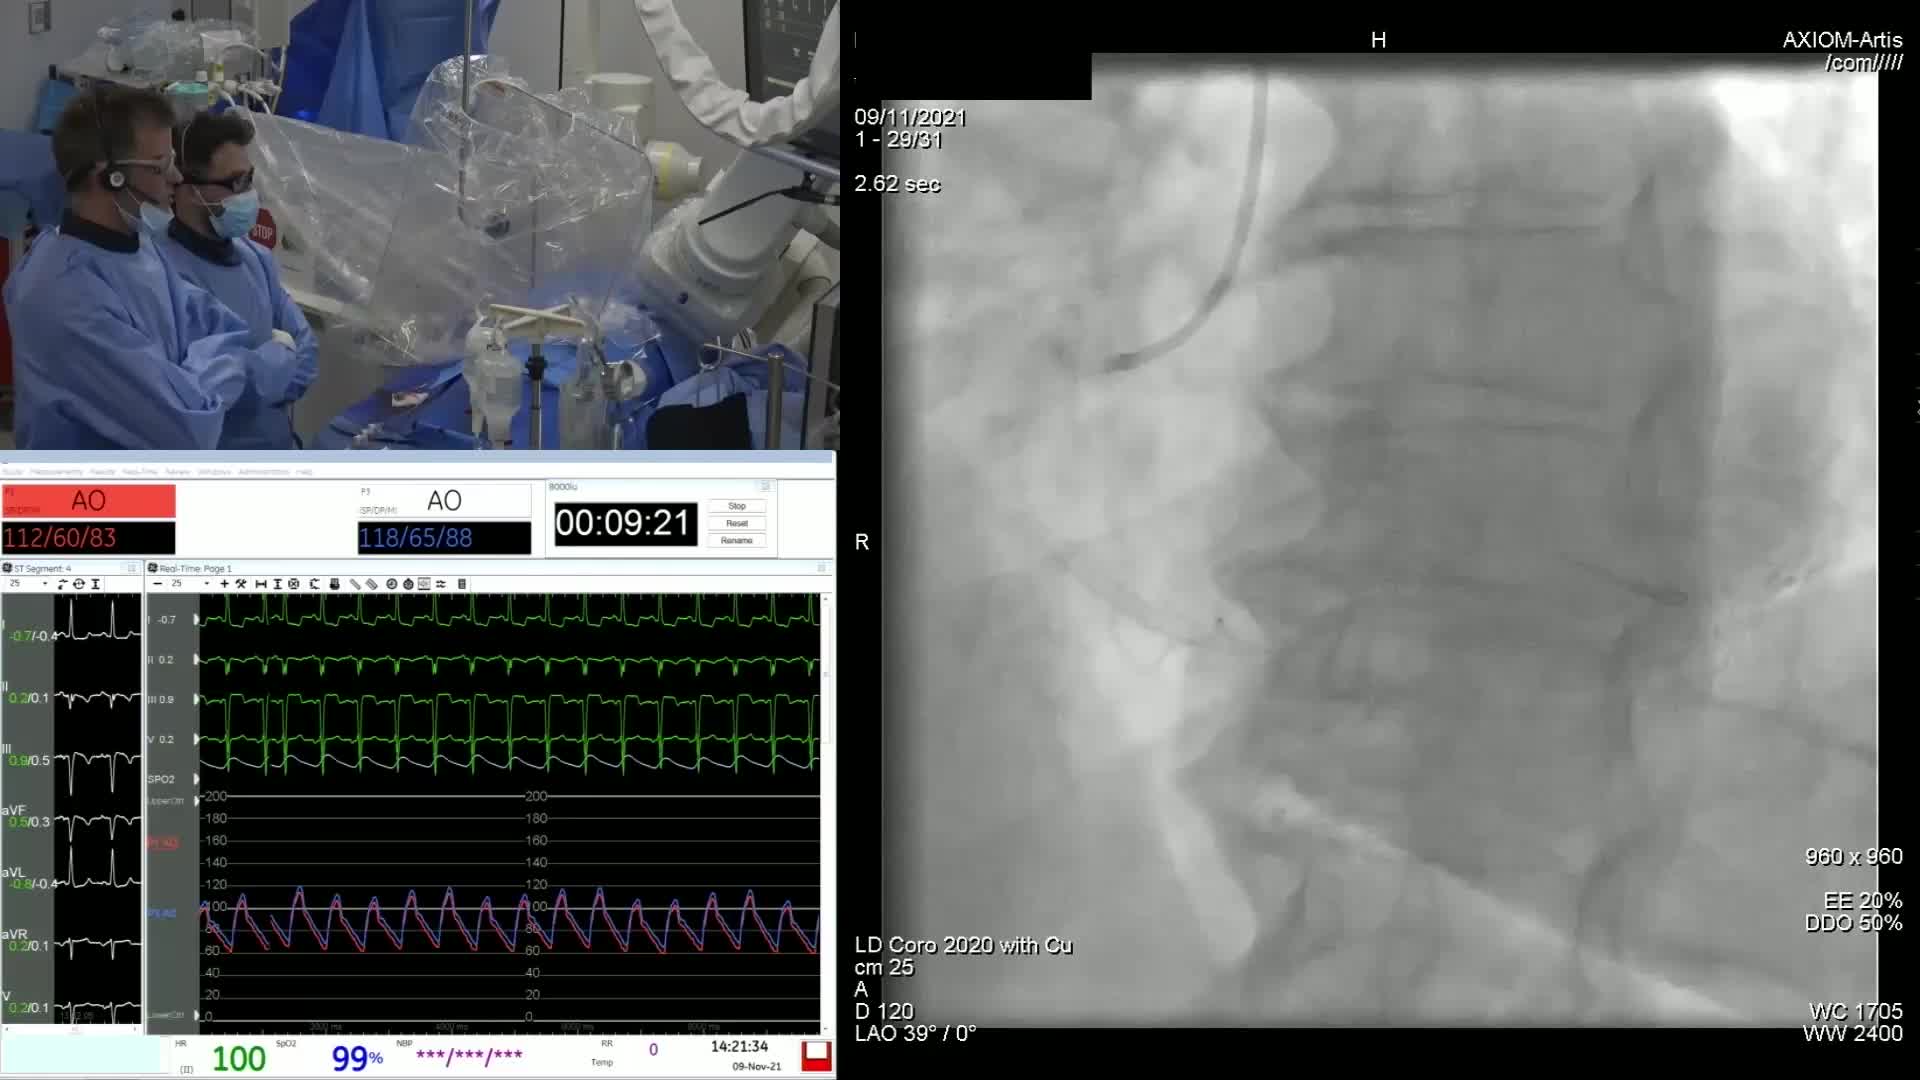

Intravascular Imaging: Foundational or Window Dressing